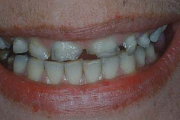

Puudub ülemine tsentraalne intsisiiv, kuid külgmised lõikehambad on juba lõikunud.

Puudub ülemine tsentraalne intsisiiv